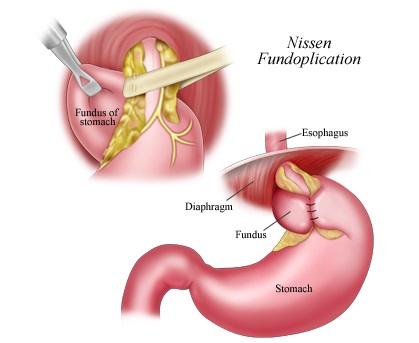

Tratamentul chirurgical al bolii de reflux gastroesofagian într-un volum fundoplication laparoscopica necesita un anumit procent de pacienti cu GERD. Obiectivele operațiunii sunt de a „strânge“ zona de joncțiune-esofagian gastric, de a genera supapă suplimentară a fundului de ochi al stomacului și, dacă este posibil, reducerea herniei hiatale a stomacului, care este frecventa la copii cu reflux gastroesofagian.

Scopul interventiei chirurgicale este de a restabili bariera antireflux, fără a crea obstacole în calea bolului. Nissen fundoplicatură - chirurgie antireflux, în care folie gastric în jurul părții inferioare a esofagului 360 °. creând o manșetă care previne conținutul gastric în esofag. Inainte de operatie, pacientii ar trebui sa fie examinate cu atenție, o atenție deosebită trebuie acordată la ultimul etaj al radiografiei tractului gastro-intestinal pentru a exclude alte posibile boli.

Principalele etape ale fundoplicatură Nissen:

- mobilizarea fundus gastrice și cardia;

- crearea tunelului din spatele esofagului;

- efectuarea de fundus a stomacului in spatele esofagului;

- creând un drum liber Nissen înălțime manșetă de 1 - 2 cm;

- fixarea manșeta la esofag și piciorul drept al diafragmei;

- excizia sacul herniei și suturarea diafragmei la picioarele HH.

Manșetă Nissen reticulat pe două rânduri sutura.

Mobilizarea fundus a stomacului și a cardia

Realizarea fundus a stomacului in spatele esofagului

Creați gratuit înălțimea Manșetă Nissen de 1 - 2 cm